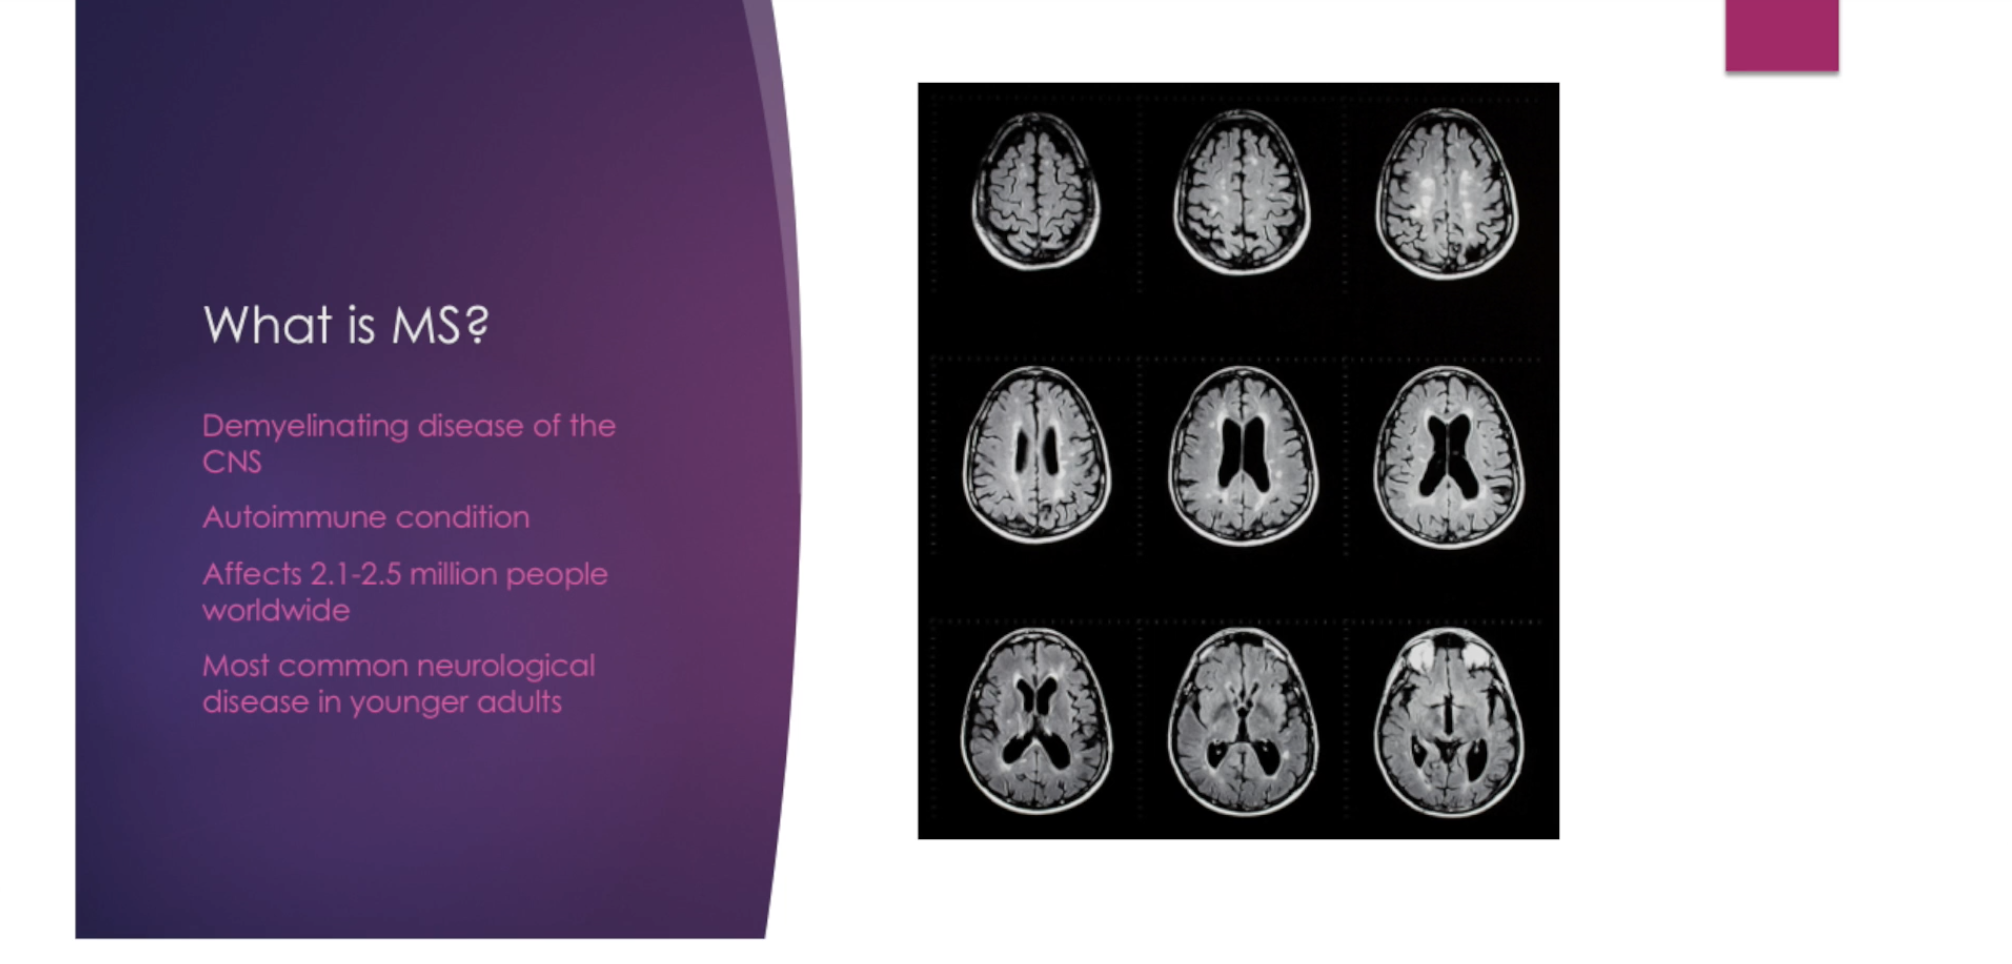

Understanding MS Workshop Introduction

To purchase this workshop, visit http://theneurostudio.com